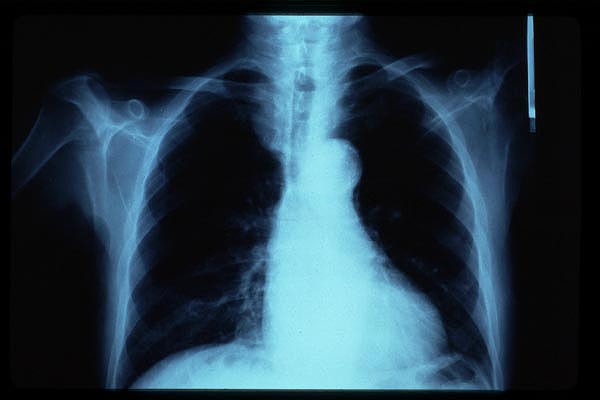

Tumoración mediastínica